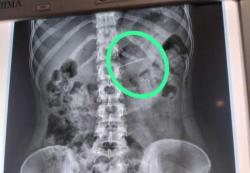

Yogya 3 tahun lalu Kondisi Terakhir Bocah yang Terkena Peluru Nyasar, Luka di Kepala Belakang Sedalam 8 Cm